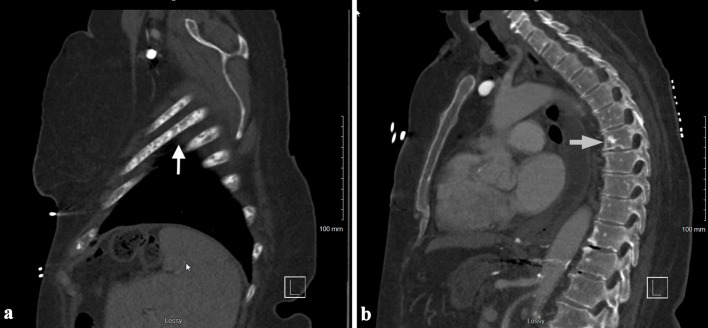

肥大细胞白血病(MCL)是一种罕见的侵袭性系统性肥大细胞增多症(SM),通常累及骨骼。这通常表现为骨质疏松伴局灶性溶骨病变和病理性骨折。成骨细胞(硬化)病变在MCL中很少见。椎体是最常见的骨受累部位,轴骨以外的病变极为罕见。以成骨细胞病变为表现的MCL在文献中已有报道,然而,在阑尾骨骼中没有成骨细胞病变的报道。在此,我们报告一例罕见的急性白血病MCL,表现为弥漫性成骨细胞/硬化性骨病变,累及肋骨、胸椎、腰椎和骨盆,无病理性骨折。

Mast cell leukemia (MCL) is a rare and aggressive form of systemic mastocytosis (SM) that commonly involves the bone. This often presents as osteoporosis with focal osteolytic lesions and pathological fractures. Osteoblastic (sclerotic) lesions are rarely seen in MCL. The vertebral bodies are the most common site of bone involvement, with lesions outside of the axial skeleton being extremely rare. MCL presenting with osteoblastic lesions has been reported in the literature, however, there are no reported cases of osteoblastic lesions in the appendicular skeleton. Here we report a rare case of acute aleukemic MCL that presented with diffuse osteoblastic/sclerotic osseous lesions involving ribs, thoracic spine, lumbar spine and pelvis without pathological fractures.